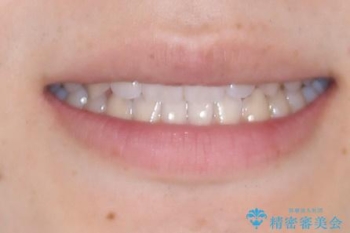

- インビザラインモデレート

- 11ヶ月

- 5-10回

そこで矯正治療と並行して**MFT(口腔筋機能療法)**を実施し、舌や口周囲筋の正しい使い方を習得していただきました。

マウスピース矯正特有の奥歯への圧下により、一時的に噛みにくさを感じる場面もありましたが、

装着時間の調整と経過観察を行うことで症状は改善し、スムーズに治療を完了しました。